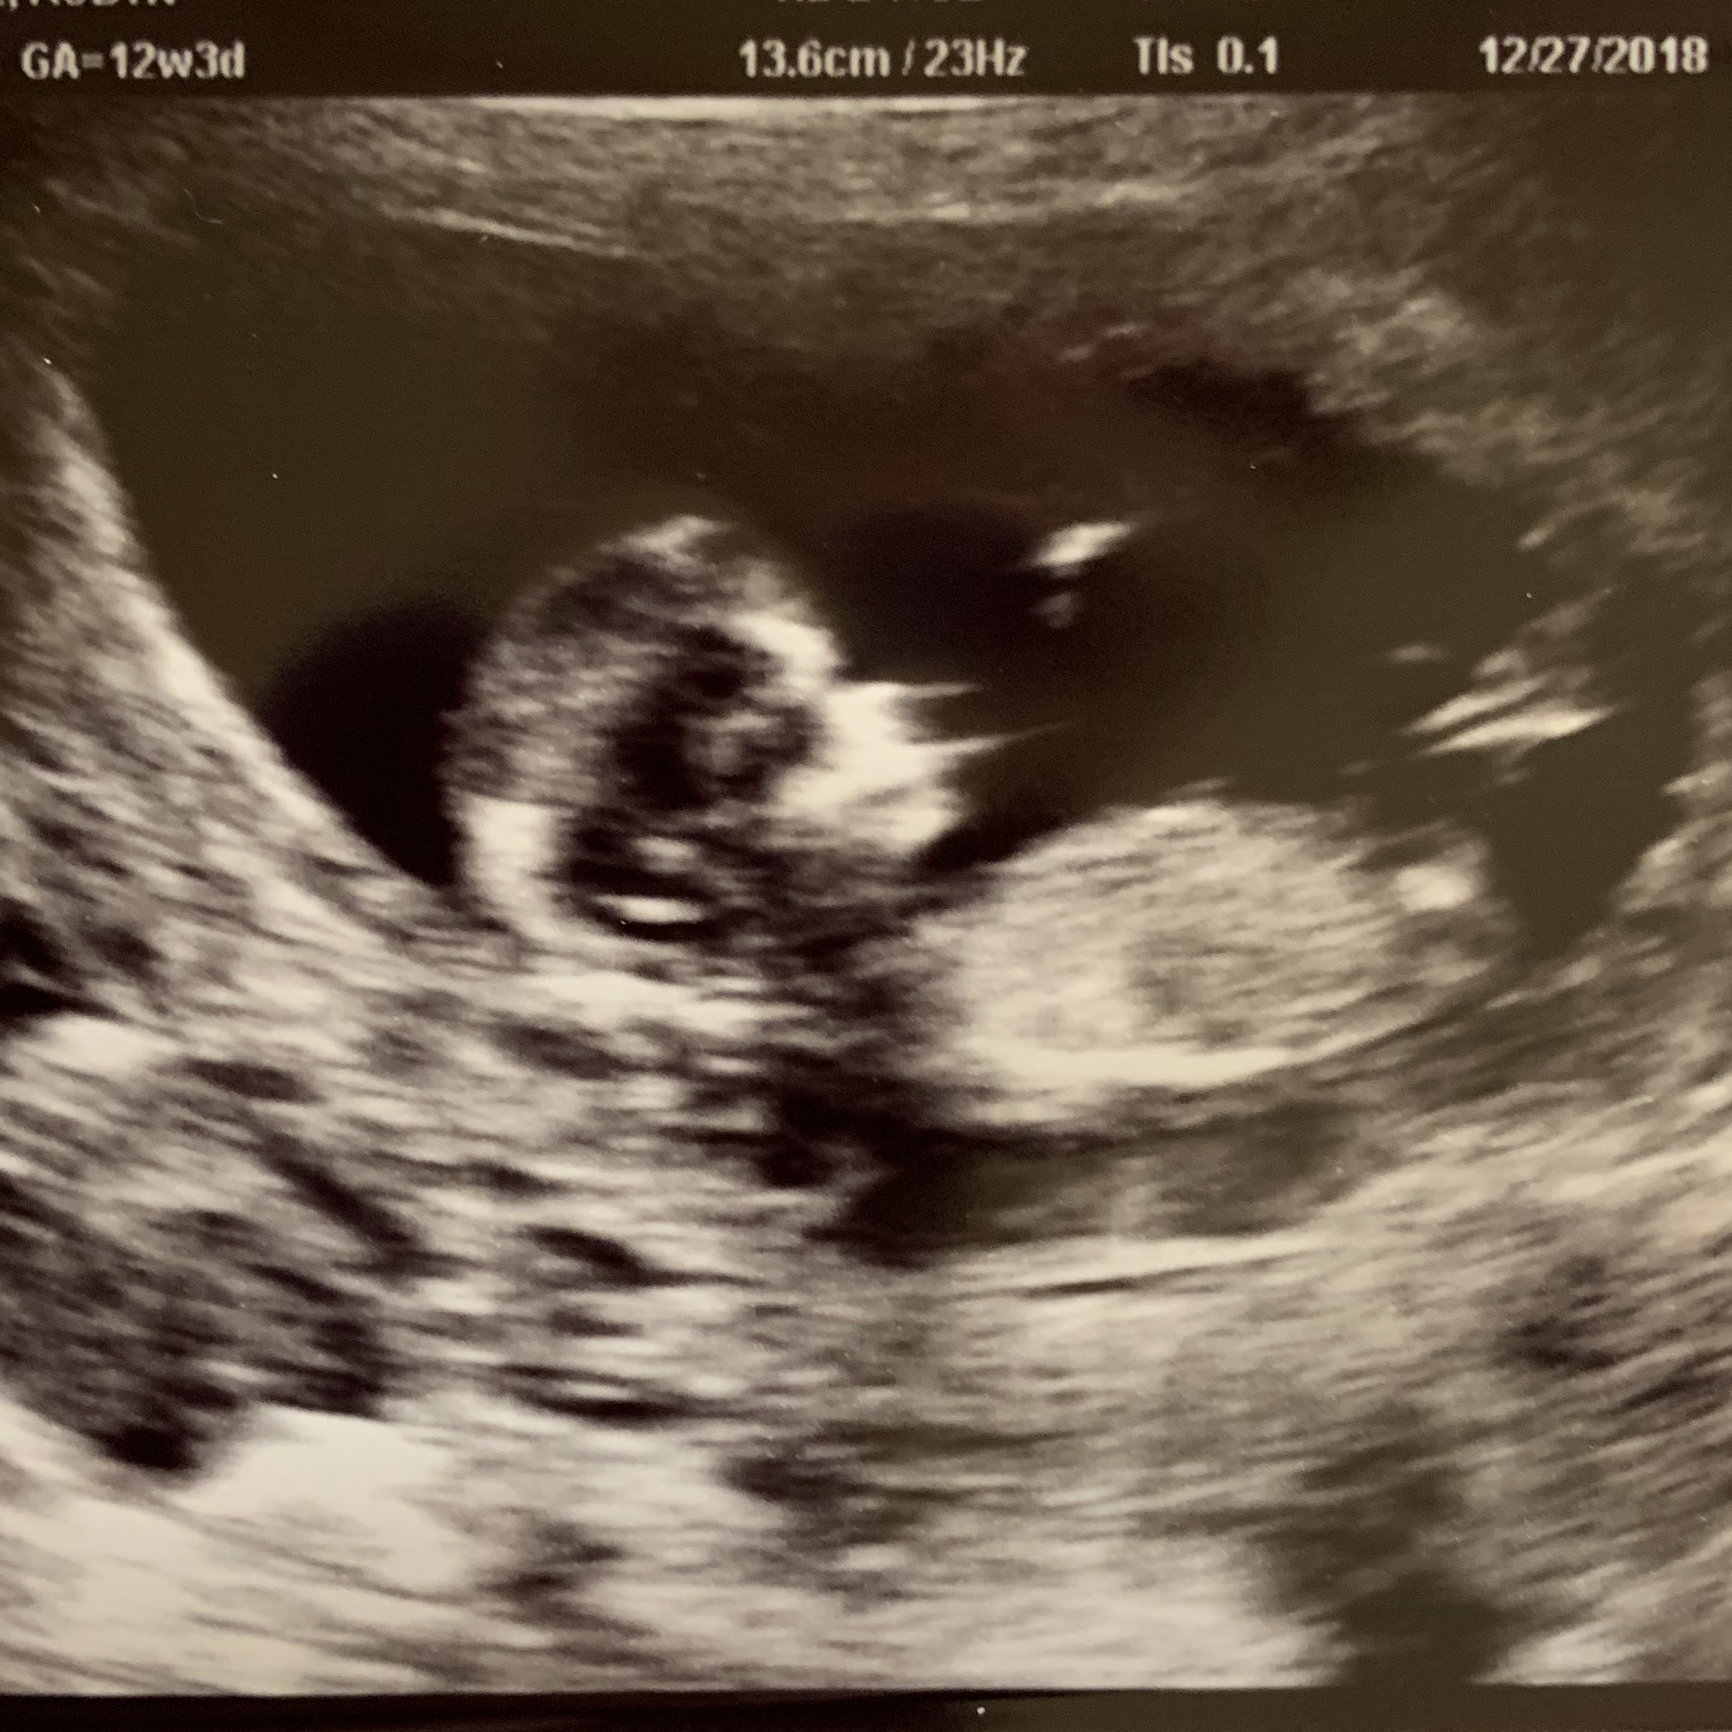

• 12 weeks 4 days!!

• It’s amazing how clear the ultrasounds get at 12 weeks!